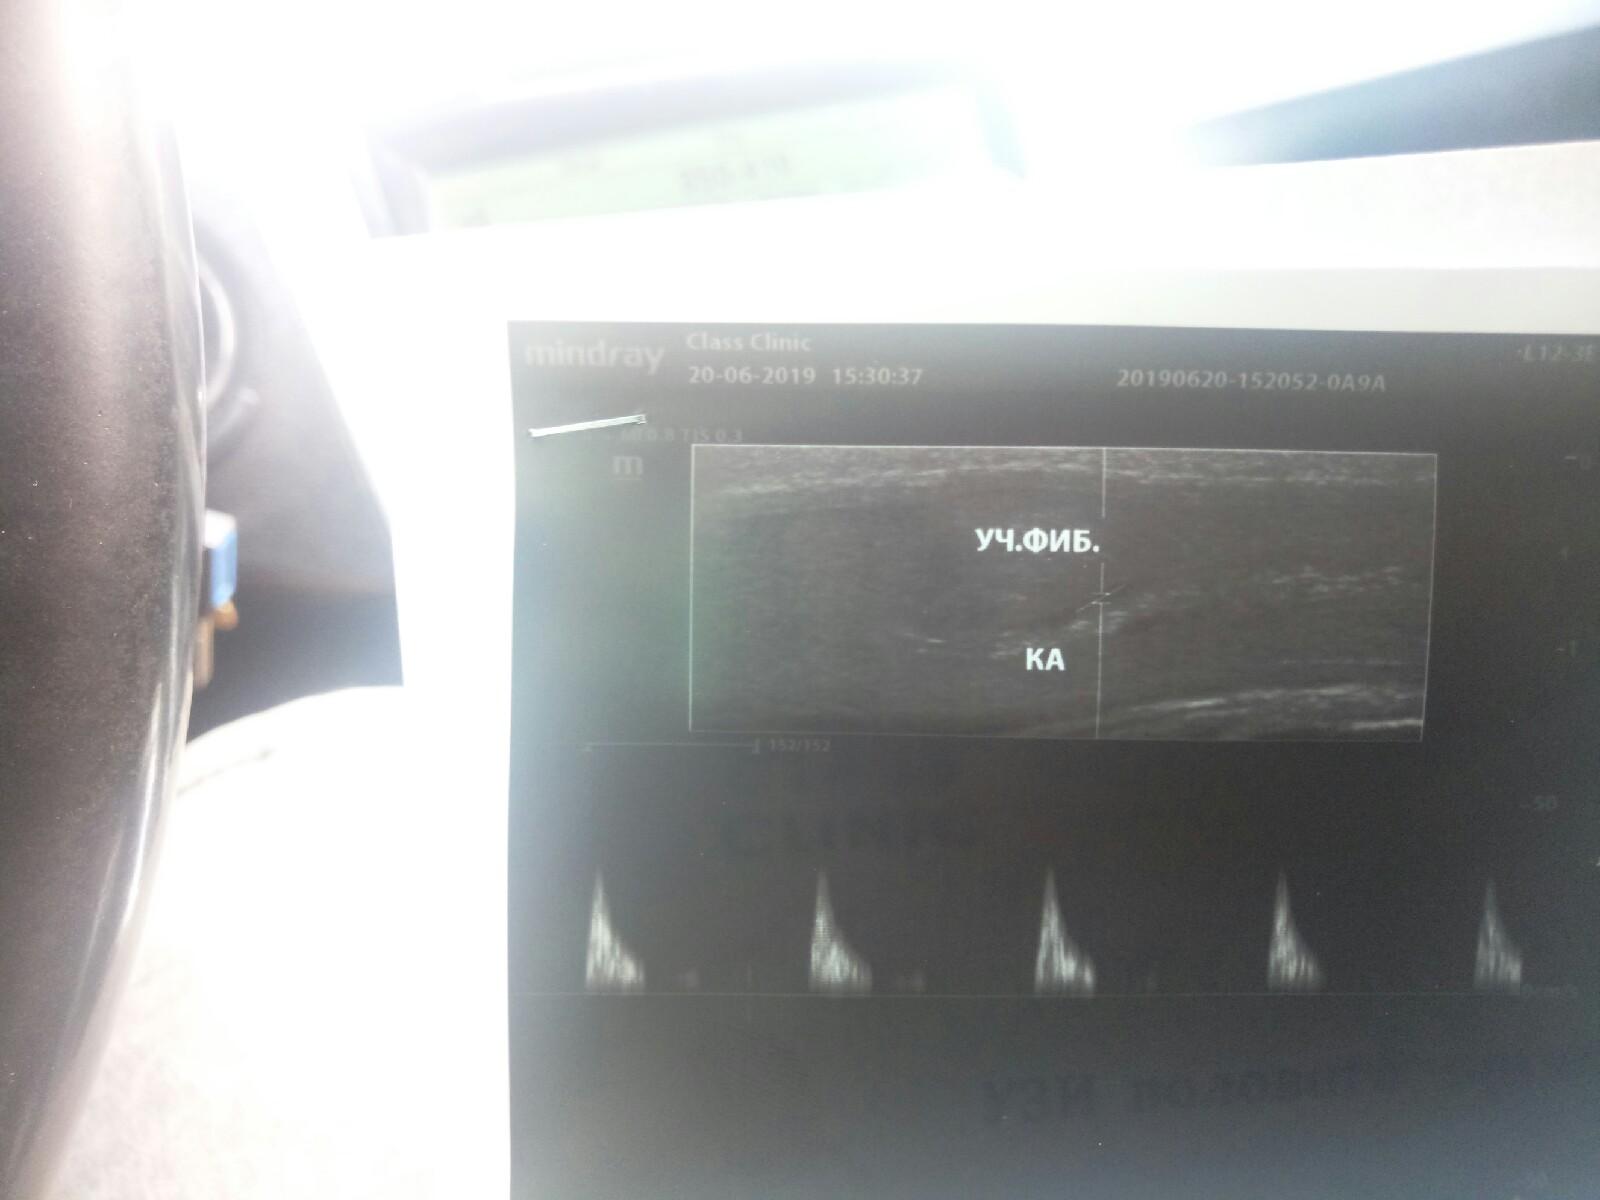

Доброго времени суток! Ситуация следующая. Катался на велосипеде, ударился членом об руль. На утро мочеиспускание с кровью. Затем мочеиспускание нормальное. Первую неделю к врачу не обращался. Затем обнаружил уплотнение у корня члена. Записался к урологу, сделал УЗИ. Уролог сказал курс электрофореза с лидазой. Прошёл курс, мазал контрактубексом. Вопрос в следующем. Прошло 2 месяца с момента травмы, эрекция отличная, мочеиспускание тоже. Но уплотнение примерно в 1 см осталось. Сделал повторное узи(файлы прилагаю). Скажите пожалуйста, какой прогноз? Возможен ли кавернозный фиброз или этот участок так и останется и всё будет хорошо? И можно ли что нибкдь сделать? очень переживаю. спасибо

Здравствуйте! Судя по результатам обследования - происходит естественный процесс рассасывания и, частично - рубцевания - в области гематомы . Осложнений на момент обследования не определяется. Прогноз благоприятный. Всё будет нормально. Удачи!